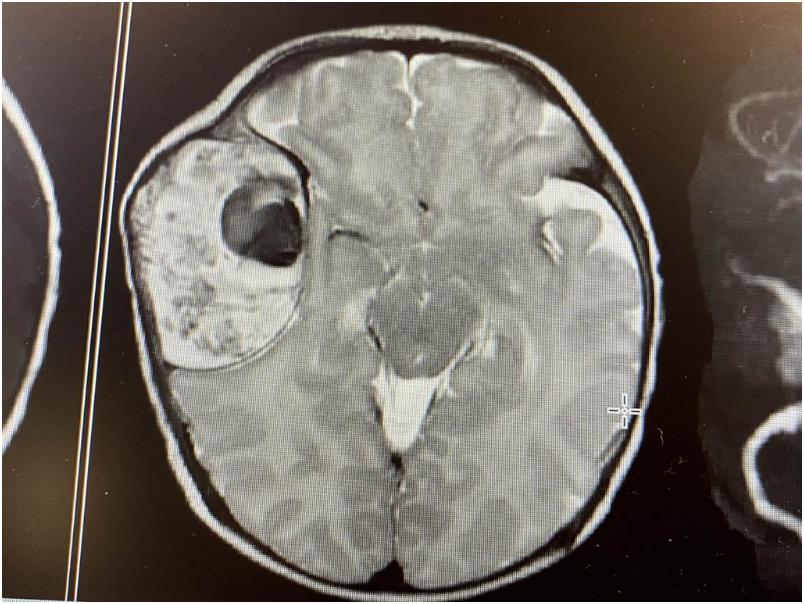

小小身体,却得承受开颅手术

医师表示,当时小俊头部右侧肿胀,使用磁振造影显示,孩子的颅骨有肿瘤,最大直径5公分,压迫到脑干、侵犯头骨,肿瘤内有出血、血管丰富、有中脑膜动脉充血。虽然切片结果显示该肿瘤为良性,但仍因压迫到脑干,被判定相当危险。医师团队在整个治疗的过程都相当谨慎,经过一系列复杂的的治疗后,孩子脑内的肿瘤变小,瘤厚度由4.5公分降至1.8公分,脑干减压。当孩子完成开颅手术后,已将肿瘤完全切除,并追踪至今。